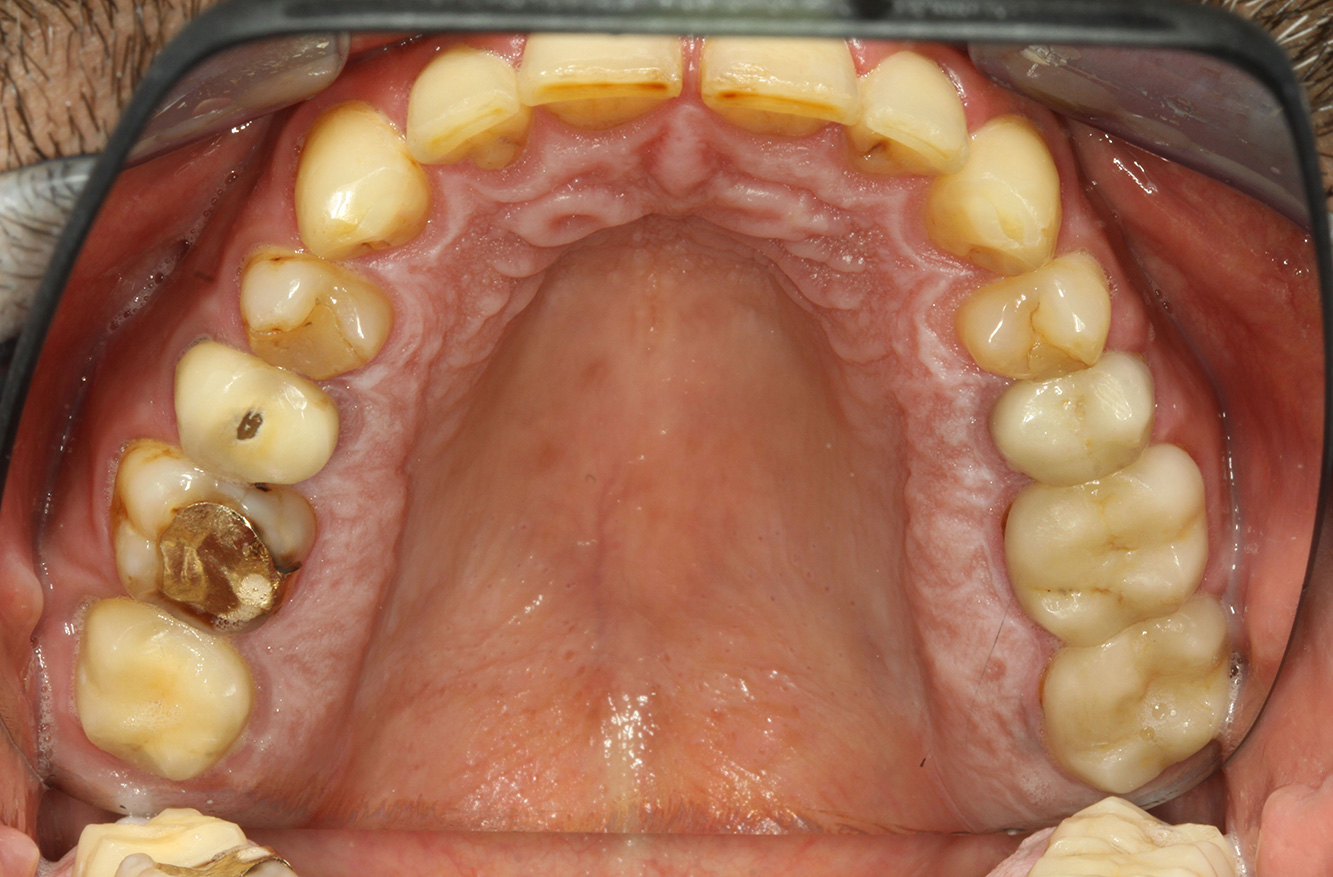

The endocarditis patient with active caries lesions*

The patient is 39 years old and has previously undergone aortic valve replacement due to valve failure and endocarditis. ASS 100 is taken regularly as an anticoagulant. In terms of lifestyle, the patient’s diet is classified as caries-promoting due to the regular consumption of sugary foods and the fact that six to seven meals are consumed daily. The patient’s oral health indicates a moderate risk of caries, with active lesions. The risk of periodontitis is low, but gingivitis is present. The following recommendations are made for prophylactic treatment.

The heart valve replacement and the history of endocarditis indicate an increased risk of complications. In order to reduce the risk of inflammation recurring, antibiotic prophylaxis is recommended (e.g. 2 g amoxicillin, 1 hour before the session). Despite the long-term blood-thinning medication, it is not expected that there will be an increased risk of bleeding in the prophylactic session.

Enough time must be allowed for the instructive/ motivational discussion. The negative impact of nutritional behaviour on oral health (9) should be clearly conveyed to the patient. With regard to the history of endocarditis, the connections between cariogenic bacteria and cardiovascular disease may also be discussed (12). This can strengthen the patient’s motivation to make a sustainable change to their diet. The discussion should convey to the patient the importance of – and motivate them to practise – good oral hygiene at home.